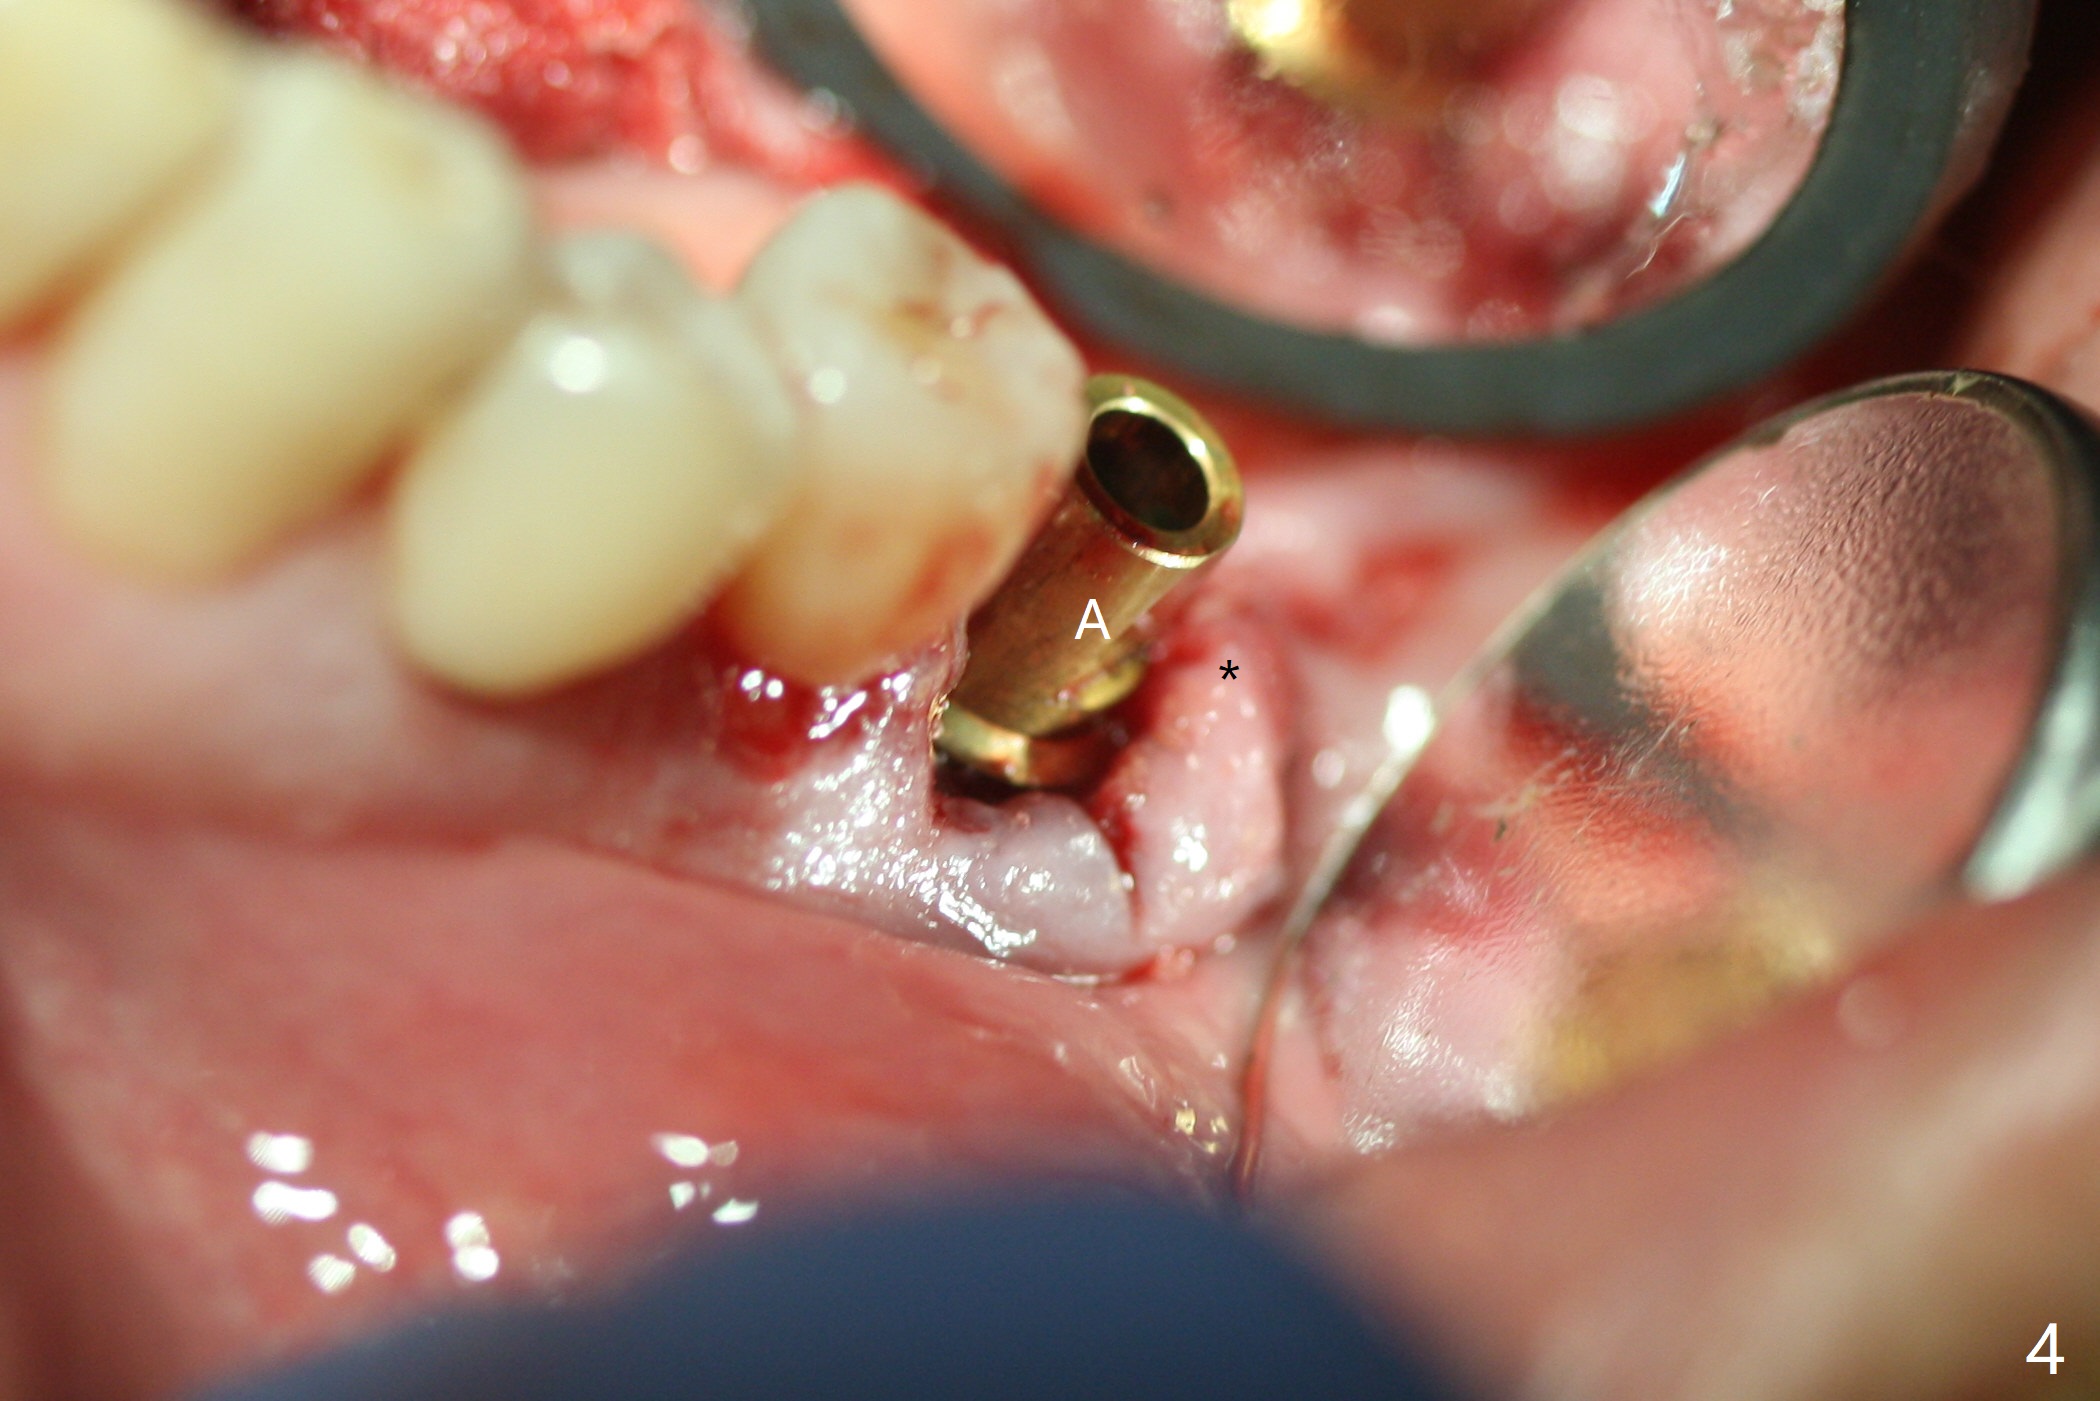

When the patient returns for #19 extraction (Fig.1), there is no 5x10 mm implant available. In fact the smaller one (4.5x10 mm) is able to achieve insertion torque >60 Ncm with more room for autogenous bone/allograft horizontally (Fig.2 *). After insertion of a definitive abutment (6.5x5.5(4) mm), more allograft is placed coronally (Fig.3 *). The gingiva that was between the mesial and distal roots before extraction (Fig.1 *) is transferred distal (Fig.4.5 *). An immediate provisional (Fig.6 P) is fabricated to close the socket opening, followed by periodontal dressing (data not shown). The latter is partially detached 2 weeks postop (Fig.7 D). When it is removed, some of possibly collagen plug is exposed distobuccally (Fig.8). When the plug is removed, some of the bone graft (Fig.9 *) is exposed distal to the provisional (P). New periodontal dressing is applied to keep the exposed graft in place. There is no apparent thread exposure 4 months postop (Fig.10). The abutment is loose 4 months post cementation, probably related to unfavorable crown/implant ratio; but when the abutment is retightened, there is a gap between it and the implant (Fig. 11 >). After relieving the proximal contact of the crown, the abutment is retightened one more time with the same gap (Fig.12 >). In fact the latter is present previously. A narrower abutment with longer cuff appears to be completely seated, probably avoiding contact with the regenerated crestal bone (Fig.13 *). If the new crown gets loose, bury a driver inside the abutment.